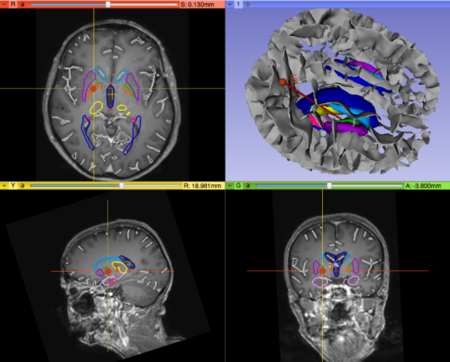

- Upgrade of the PyDBS modules for Parkinson Surgery to Slicer4.4

- Upgrade Slicer plugins from 4.3 to 4.4